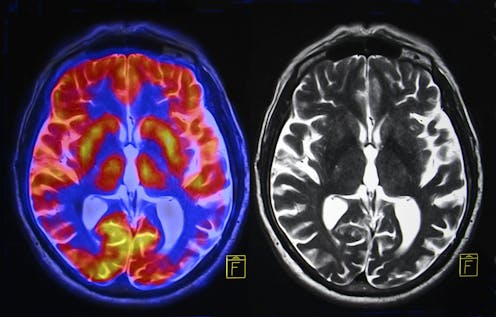

In 2000 I first suggested that the way the “early visual cortex” – the location where visual information from the eye first impacts the cortex – processes information gave rise to the ability to engrave simple patterns. We know that this area has neurons coding for edges, lines and “T” junctions. As distilled forms, these shapes preferentially activate the visual cortex.

It’s easy to see how this may have come about. Lines, angles and intersections are the most abundant features embedded in the natural environment – they provide crucial first cues to the layout of objects. Our brain’s ability to process them is shared by other primates, but the human brain is also able to respond to these cues proactively using “Gestalt principles” – rules that enable the mind to automatically perceive patterns in a stimulus. This helps it construct basic forms that are fed forward to the higher-order visual areas of the brain, which can process them in a way so we can experience them as real objects.

These developments therefore enabled the brain to reuse the visual cortex for an entirely new purpose. Ultimately, it could have created a new process in the brain that exploited the visual cortex, giving rise to a visual word form area and connecting with speech areas incrementally over time.